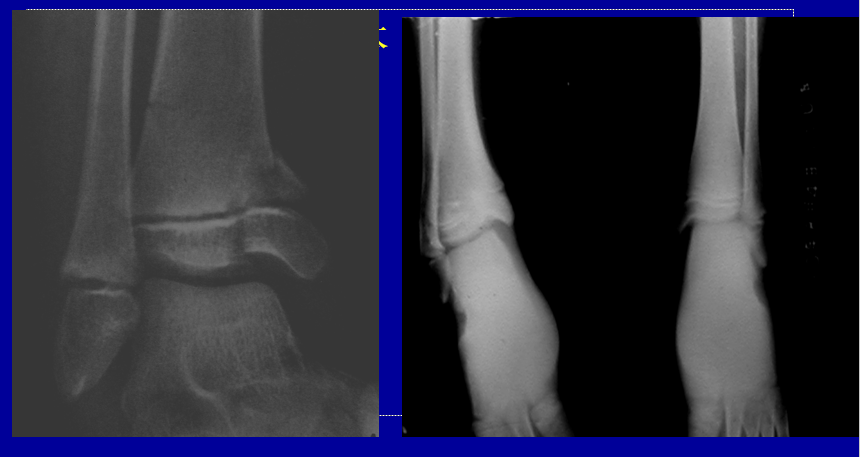

生长停滞 growth arresy部分生长停滞:最常见,可引起肢体成角畸形和短肢畸形。全部生长停滞:少见,短肢畸形。

部分生长停滞分型A 周围型  占60%B 中央型     占20%C 混合型        占20%